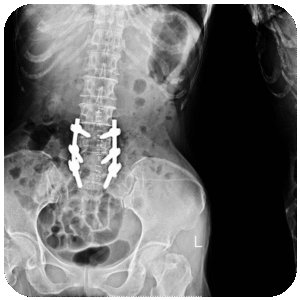

Es un defecto congénito en el cual los huesos de la columna no se forman totalmente, esto provoca un conducto raquídeo incompleto en el cual la médula y las meninges sobresalen de la espalda del niño.

Se corrige mediante un procedimiento quirúrgico llamado meningoplastia, que es el cierre quirúrgico del defecto.